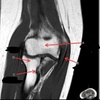

1

Not at all

2

3

4

5

Perfectly

11

Q

What is letter A?

A

ANTERIOR LABRUM